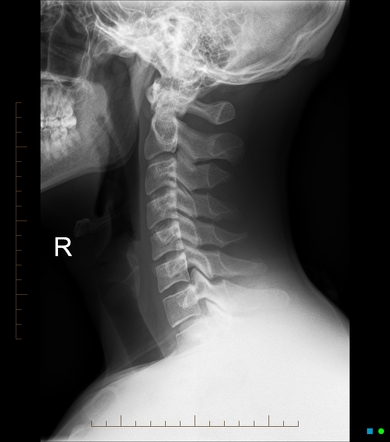

The Essential Role of X-Rays in Ensuring Safe and Effective Chiropractic Care

Chiropractic care plays a vital role in promoting good health, alleviating pain, and addressing muscle and bone issues. X-ray imaging is necessary for your Chiropractic doctor to better understand the spine and musculoskeletal structures, prevent harmful adjustments and to optimize treatment results.